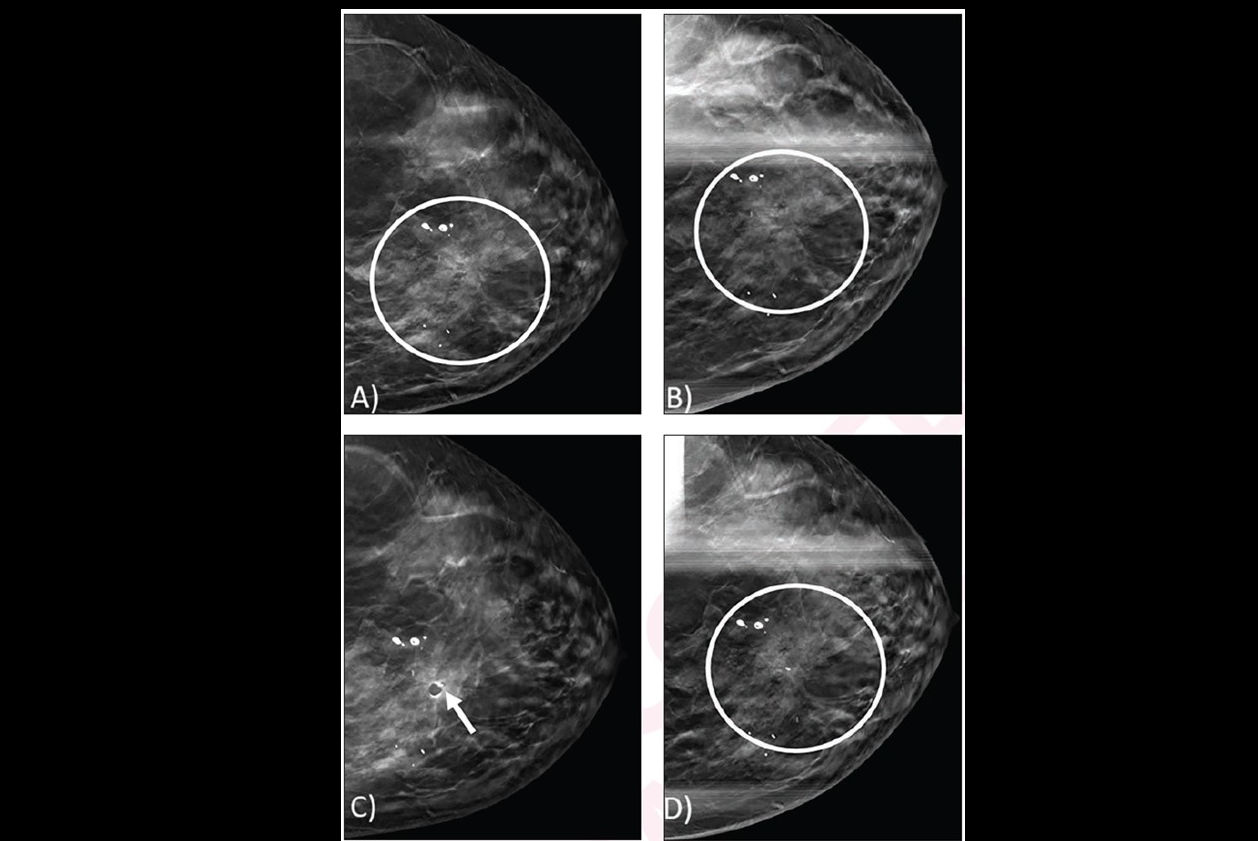

The use of DBT continues to rise in popularity among breast imaging facilities worldwide. But little is known about the long-term benefits and harms of DBT screening with or without supplemental breast MRI, the researchers explained, noting that this information is needed for clinical and policy discussions.

Stout and co-authors sought to project long-term population-based outcomes for breast cancer mammography screening strategies, including DBT and digital mammography, with or without supplemental MRI by breast density. They evaluated starting ages for screening at 40, 45, or 50 through age 74. and used three breast cancer simulation models from the Cancer Intervention and Surveillance Modeling Network (CISNET), informed by U.S. Breast Cancer Surveillance Consortium (BCSC) data.